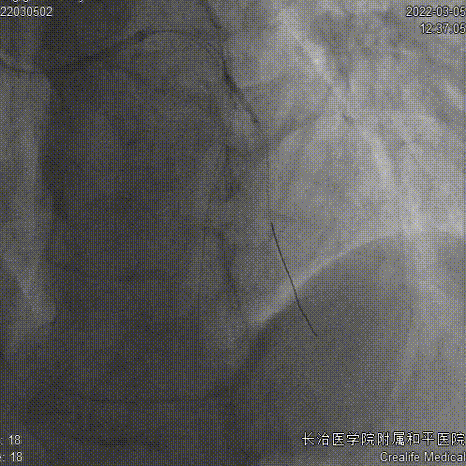

2.5x10mm切割球囊

残余狭窄、肌桥

药物球囊2.75x35mm、Telescope™导引延长导管